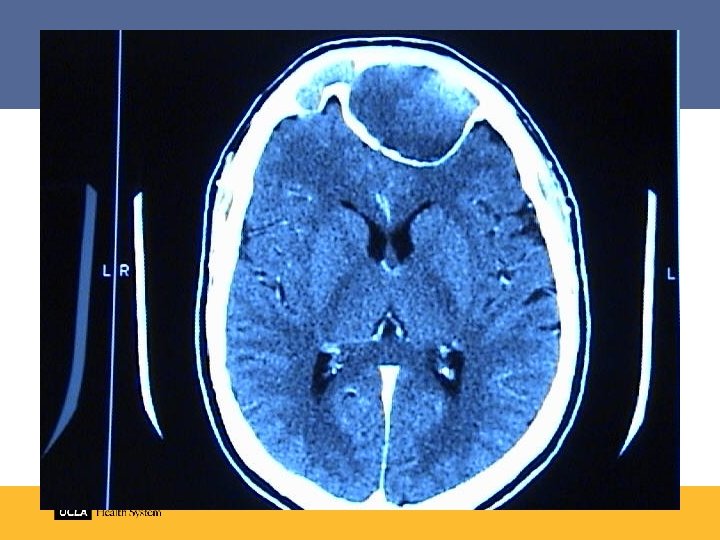

Complications of sinusitis • Periorbital cellulitis • Preseptal cellulitis/abscess • Orbital cellulitis • Orbital abscess • Cavernous sinus thrombosis